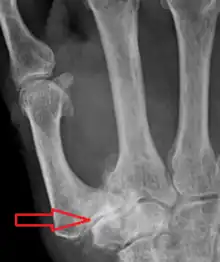

TMC OA is diagnosed based on symptoms and signs.[8] Radiographs can confirm the diagnosis and the severity of TMC OA. Other diagnoses in this region include scaphotrapezial trapezoid arthritis and first dorsal compartment tendinopathy (De Quervain syndrome) although these are usually easy to distinguish.

TMC OA severity was classified by Eaton and Littler which can be simplified as follows:[21][22]

Stage 1:

- slight widening of the joint space

- < 1/3 subluxation of the joint (in any projection)

Stage 2:

- Osteophytes, < 2 mm in diameter, are present. (usually adjacent to the volar or dorsal facets of the trapezium)

Stage 3:

- Osteophytes, > 2 mm in diameter, are present (usually adjacent to the volar and dorsal facets of the trapezium)

- Slight joint space narrowing

Stage 4:

- Narrow joint space

- Concomitant scaphotrapezial arthritis

A simpler classification is no arthritis, some arthritis, and severe arthritis.[23] This simpler classification system omits the potentially contradictory details of the Eaton/Littler classification and keeps scaphotrapezial arthrosis separate.